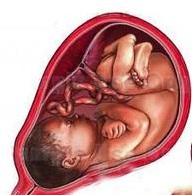

怀孕第20周

怀孕第20周 -

怀孕第21周

怀孕第21周 -

怀孕第22周

怀孕第22周 -